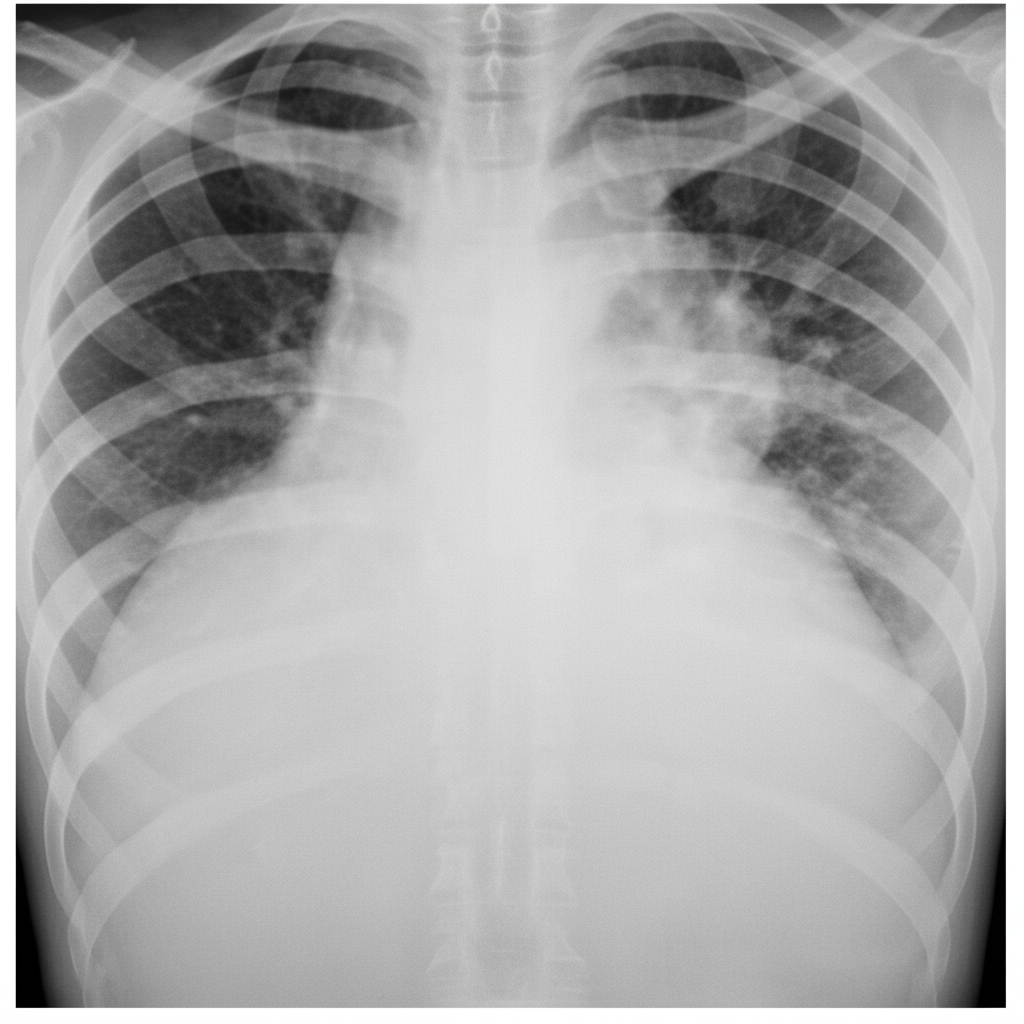

A patient presented with sudden onset difficulty in breathing with RR 28/min, normal blood pressure. X-ray was taken which is given below. What is the diagnosis?

Explanation: ***Hydro-pneumothorax*** - The chest X-ray clearly shows a **horizontal air-fluid level** in the right hemithorax, indicating the presence of both air (pneumothorax) and fluid (hydrothorax) within the pleural space. - The patient's sudden onset **difficulty in breathing** and **tachypnea (RR 28/min)** are consistent with significant lung pathology like a hydropneumothorax, which compromises lung function. *Pneumothorax* - A simple pneumothorax would show only **air in the pleural space**, characterized by a visible visceral pleural line and absence of lung markings beyond it. - While there is air present, the prominent **fluid level** rules out a diagnosis of pneumothorax alone. *Pleural effusion* - Pleural effusion presents as a **blunting of the costophrenic angles** and a meniscus sign, where fluid conforms to the shape of the thorax. - This image shows a **straight air-fluid level**, not a typical meniscus, indicating the presence of air in addition to fluid. *Consolidation* - Consolidation refers to the **filling of alveolar spaces with fluid or exudate**, appearing as an opacification within the lung parenchyma. - Consolidations typically do not present with a **horizontal fluid level** in the pleural space; they are intraparenchymal.